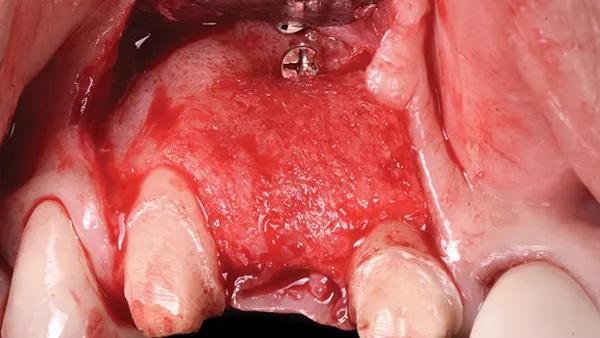

Затем с помощью 3-миллиметрового круглого твердосплавного бора выполнили проникновение в костный мозг в буккальной пластине (Фото 4). Аутогенная кость забирали по косой линии восходящей ветви нижней челюсти с помощью одноразового костного скребка. На реципиентном участке выполнили один периостальный освобождающий разрез с последующим растягиванием субпериостальных пучков волокон, чтобы облегчить продвижение лоскута и получить первичное ушивание без натяжения.

Перед установкой костного трансплантата и адаптацией мембраны к дефекту несколько 3-мм винтов для фиксации мембраны (Pro-fix, Osteogenics) закрепили в апикальном отделе дефекта, подлежащего трансплантации (Фото 4). Эти винты устанавливали по описанному выше протоколу и размещали с осторожностью, чтобы избежать случайного проникновения в анатомические структуры, такие как корни соседних зубов и канал нижнего альвеолярного нерва. Передний винт устанавливали медиально к краю дефекта, второй — дистальнее дефекта, а третий — в апикальной части дефекта, на середине мезиодистальной протяженности дефекта.